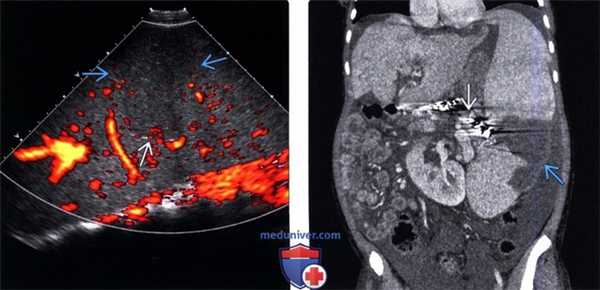

(Левый) При энергетической УЗ-допплерографии селезенки в продольной плоскости определяется центральная четко отграниченная клиновидная область относительной гипоэхогенности . В зоне инфаркта регистрируется ослабленный (но не отсутствующий) сигнал энергетического допплера.

(Правый) Пациент с последней стадией поражения печени и портальной гипертензией, массивным асцитом. КТ с контрастным усилением. На коро-нальной томограмме той же зоны определяется спленомегалия и центральный инфаркт селезенки. Наблюдается полостчатый артефакт, вызванный металлической эмболизирующей спиралью (после терапевтической эмболизации селезеночной артерии).